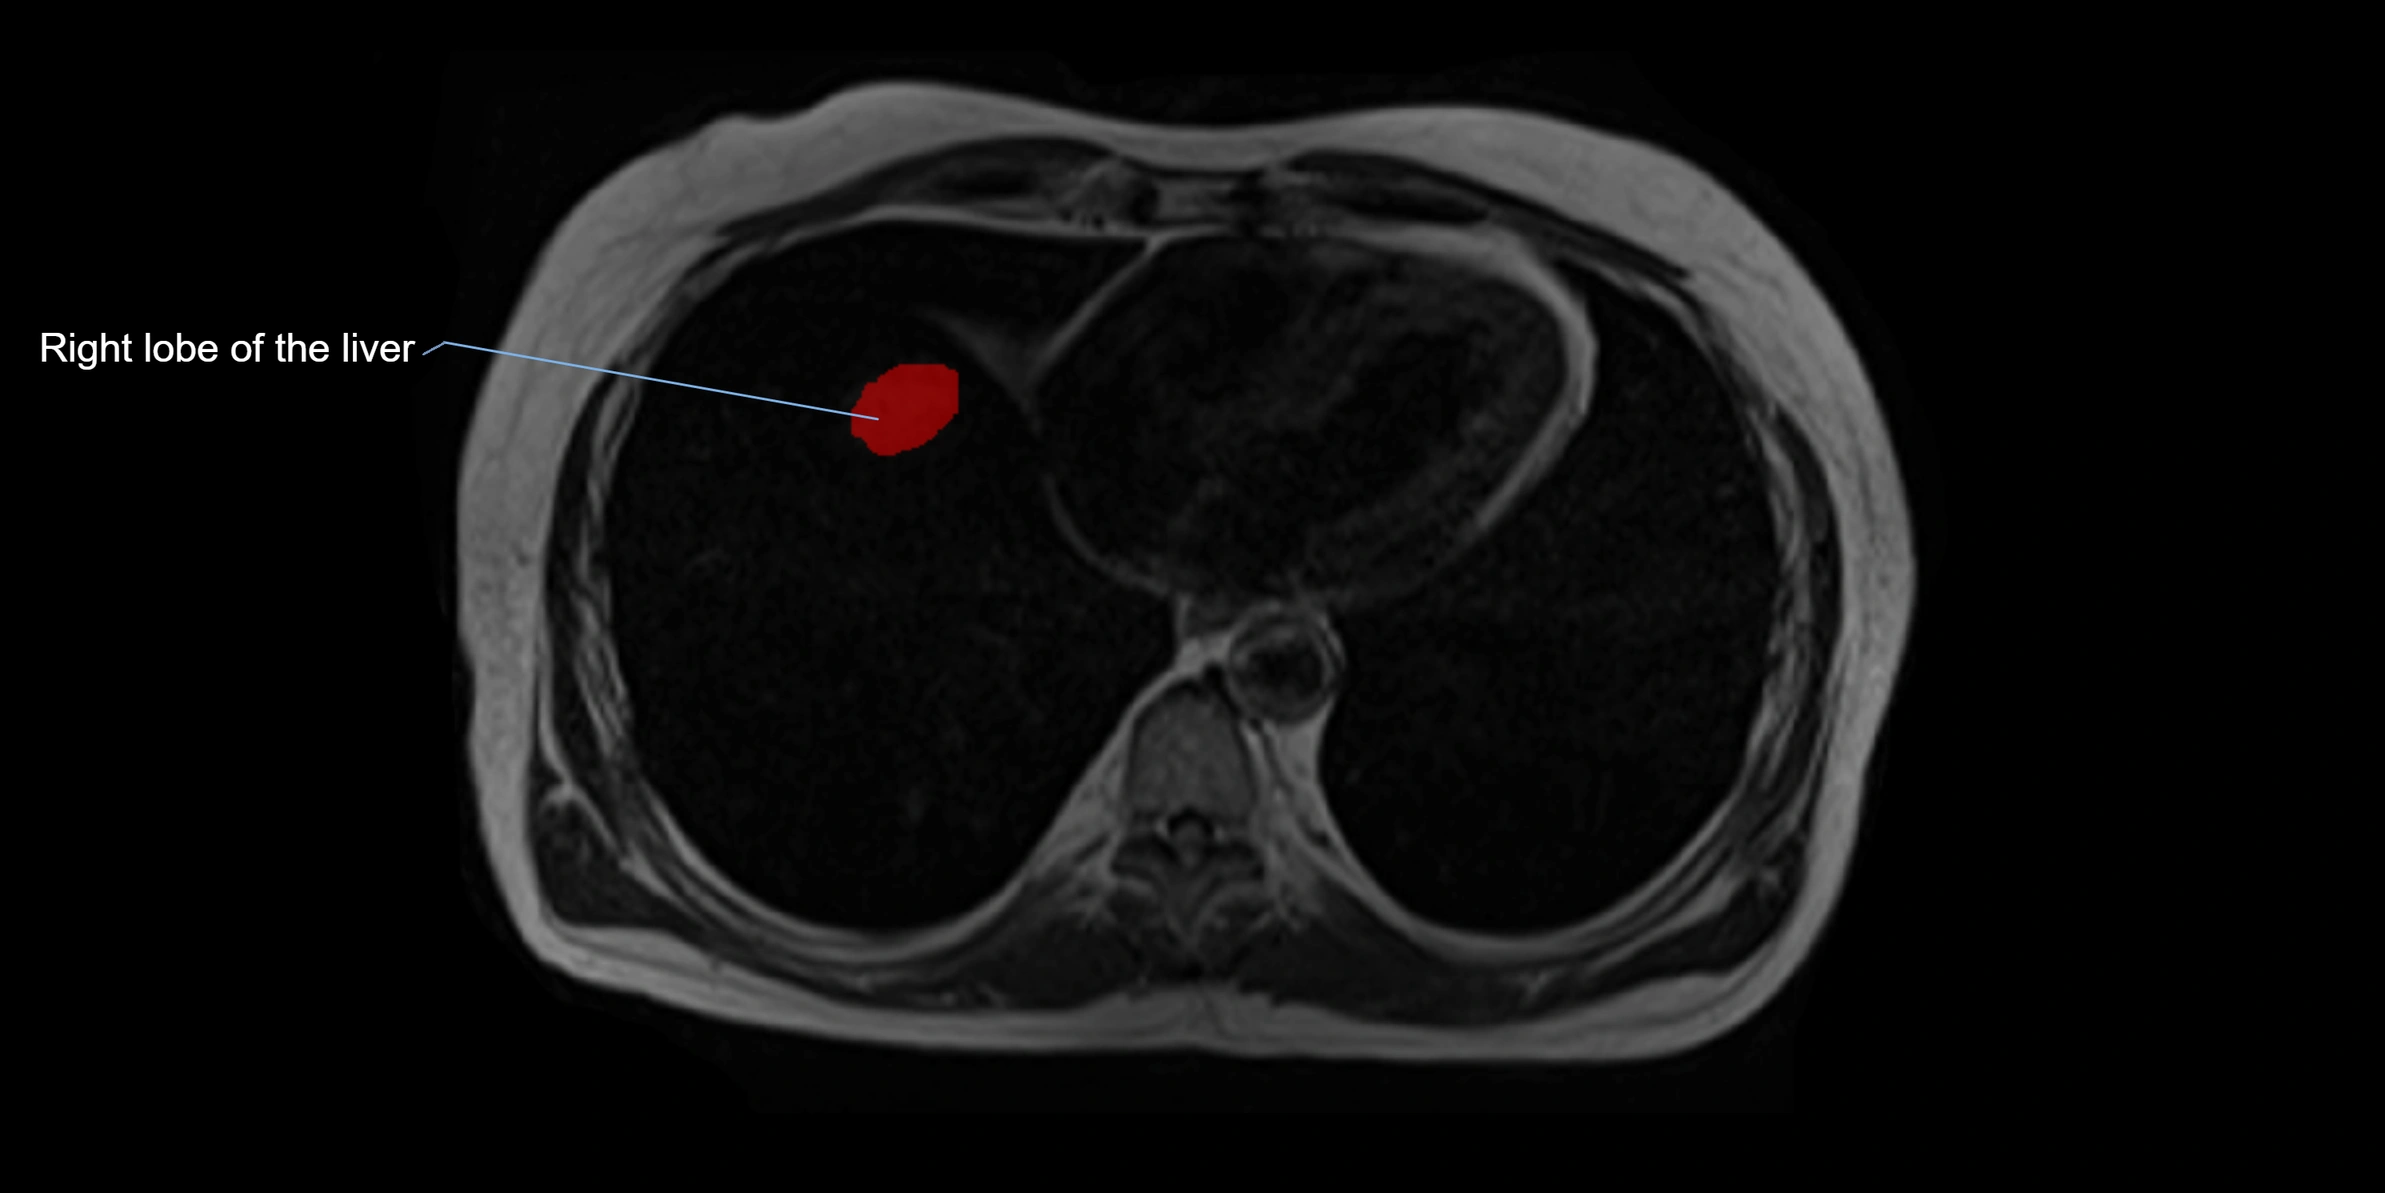

The caudate lobe of the liver is a distinct anatomical subdivision of the liver, designated as segment I in Couinaud’s classification. It lies on the posterior surface of the liver, between the fissure for the ligamentum venosum (left boundary) and the groove for the inferior vena cava (IVC) (right boundary). Superiorly, it is related to the posterior liver surface, and inferiorly it is separated from the left lobe by the porta hepatis.

This anatomical autonomy makes the caudate lobe especially significant in liver surgery, transplantation, and hepatic venous outflow obstruction syndromes (e.g., Budd–Chiari syndrome). Enlargement of the caudate lobe is a characteristic imaging feature in chronic liver disease and cirrhosis.